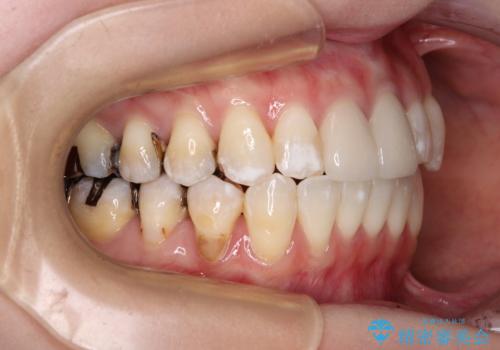

- 前歯のデコボコとセラミッククラウン周りの黒い縁を気にして来院された患者様です。

前歯の黒い縁は、矯正治療後にオールセラミッククラウンにて改善することとしましたが、いち早く目立たなくしたいとのことで、事前に矯正治療用仮歯に置き換えてから矯正治療を開始しました。

前歯を早々に仮歯に置き換えたことで、矯正治療に意欲的に臨んでくださいました。

口元が前方に突出することもなく、綺麗に仕上げることができました。